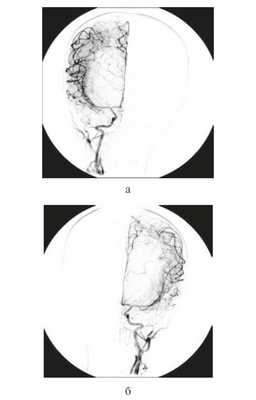

После проведенной интенсивной терапии и стабилизации состояния ребенка для уточнения степени кровоснабженности опухоли была произведена тотальная ангиография сосудов головного мозга — сосудистой сети опухоли не выявлено, дислокация сосудов мозга по гидроцефальному типу (рис. 3).

Рисунок 3. Тотальная церебральная ангиография сосудов головного мозга у грудного ребенка 11 мес c гигантской внутрижелудочковой опухолью. Сосудистой сети опухоли не выявлено, дислокация сосудов мозга по гидроцефальному типу (a — справа; б — слева).